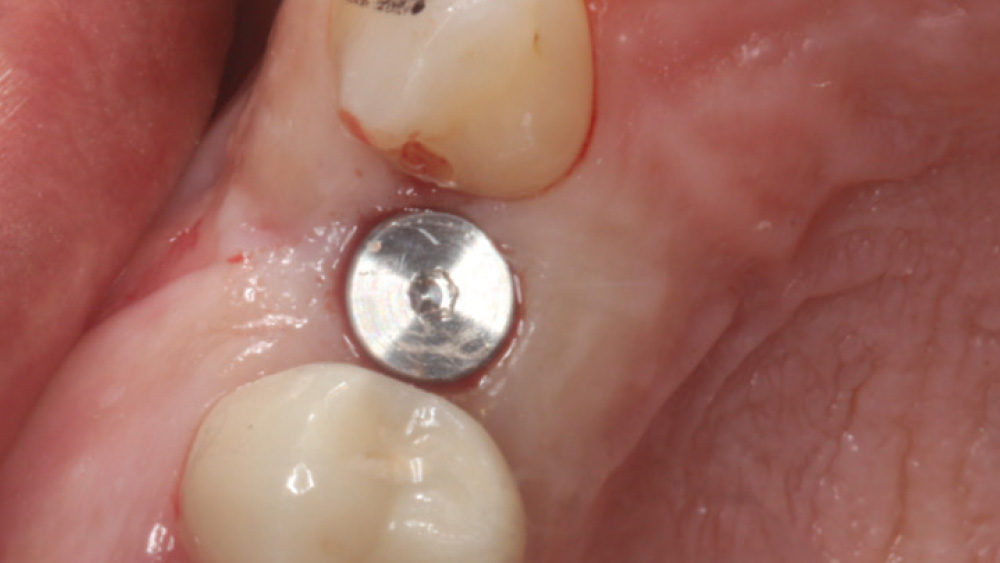

In contrast, with a flapless procedure, a tissue punch is used to gain access to the bone through the gingiva, minimizing postoperative discomfort by eliminating incisions in the mucosal tissue. Whenever mucosal tissue is incised, prostaglandin and histamine are released, resulting in potential postoperative swelling and pain. Therefore, when there is an adequate width of attached gingiva on the facial aspect of an implant site, a flapless procedure may be indicated, eliminating any suturing requirements.

Advantages of Flapless Procedure

• Simple, efficient access to the implant site

• Postoperative swelling and discomfort are minimized

• No suturing required

CASE REPORT

The following case, which I performed alongside Dr. Stephanie Tilley of Pensacola, Florida, illustrates the use of both surgical techniques for the same patient, who presented with edentulous spaces in the areas of both right and left maxillary first bicuspids. Due to varying soft-tissue volume on each side of the arch, implant surgery was performed using a flapless procedure for one site, while the attached gingiva was reflected to expose the available hard tissue for the other. As a result of proper site evaluation, treatment planning and restorative-driven implant placement, both surgical techniques led to successful outcomes for the patient.